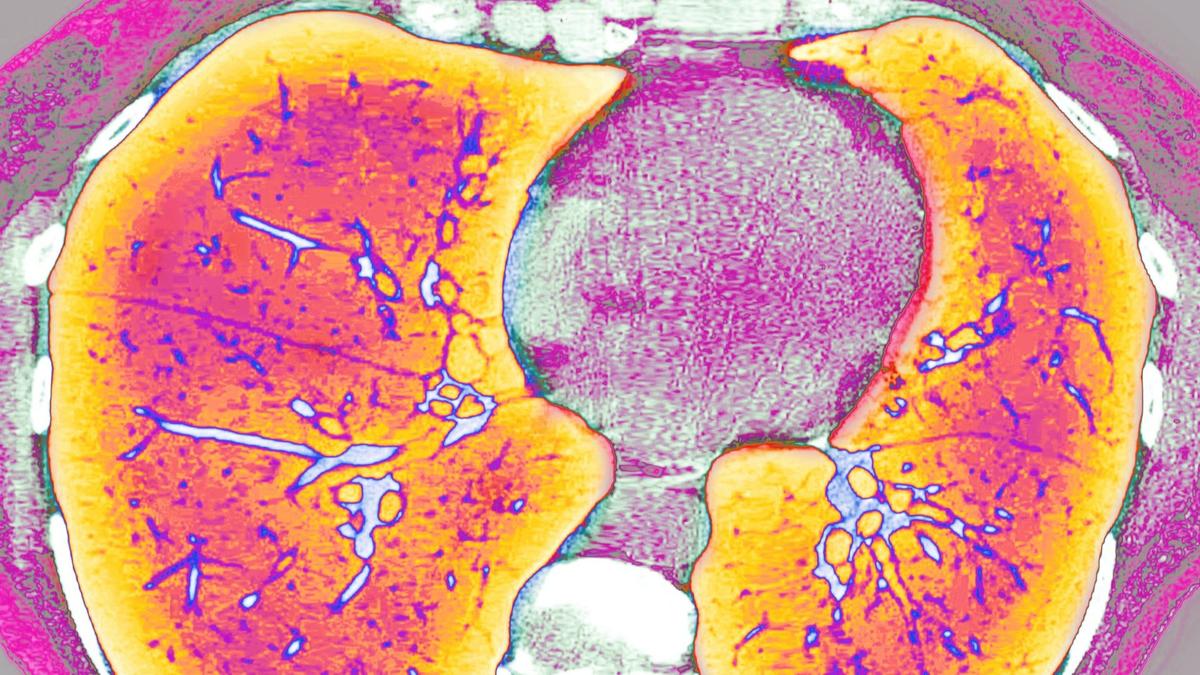

Куда уходит фарма Российские пациенты с муковисцидозом жалуются, что в стране пропал жизненно важный препарат «Пульмозим». Компания-производитель отрицает, что это из-за войны и санкций